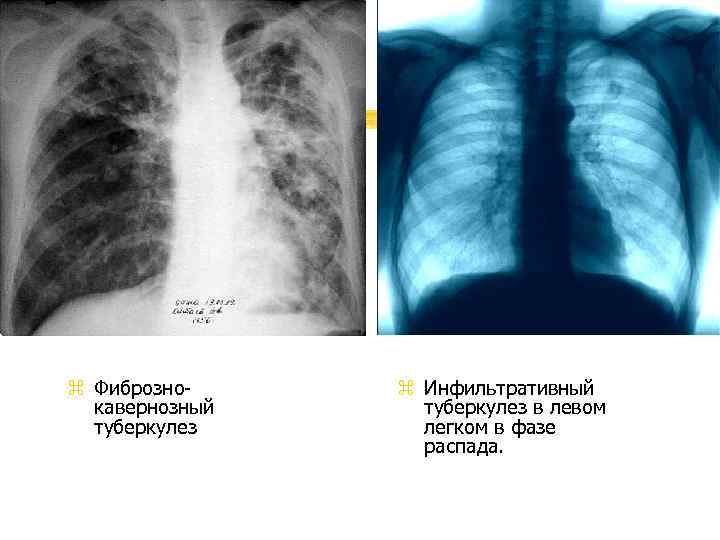

Симптомы и лечение инфильтративного туберкулеза легких

Раздел: Снимки-откровения